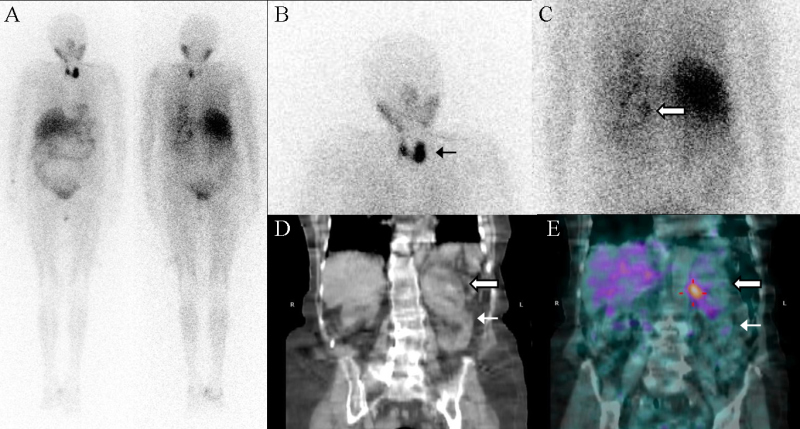

Mujer hipertensa de 86 años con masa suprarrenal izquierda detectada en ecografía y TC de abdomen, realizadas por dolor abdominal. Como antecedentes familiares presentaba un primo y dos sobrinos con neoplasia endocrina múltiple (MEN), variante MEN 2A. La analítica mostró elevación de catecolaminas en orina. Se realizó gammagrafía de médula suprarrenal para caracterización de la masa adrenal tras administración de 370 MBq de 123I-MIBG, vía intravenosa, con bloqueo previo de la captación de la tiroides con lugol. Se adquirieron imágenes planares (rastreo corporal y gammagrafía localizada de abdomen) y SPECT/TC de abdomen a las 4 h y 24 horas de la inyección del radiotrazador. Se visualizó una masa adrenal izquierda con captación heterogénea de radiotrazador y con un depósito focal patológico de 123I-MIBG en el seno de la misma, compatible con la presencia de tejido cromafín. Además se observó, tanto en las imágenes precoces como en las tardías, un aumento patológico de captación de 123I-MIBG en la glándula tiroides, de mayor intensidad en el lóbulo izquierdo (figura 1). El diagnóstico citopatológico de la eco-PAAF de dicho lóbulo fue de carcinoma medular de tiroides (CMT). Debido a la edad de la paciente y ante el riesgo quirúrgico, no se realizó biopsia ni cirugía de la masa suprarrenal. Se decidió tratamiento farmacológico con alfabloqueantes con buena respuesta, confirmando la sospecha de feocromocitoma.

La gammagrafía con 123I-MIBG se utiliza fundamentalmente para el estudio de la médula adrenal, fijándose el radiotrazador en tumores derivados de la cresta neural: neuroblastomas, feocromocitomas y paragangliomas. La 123I-MIBG también tiene afinidad por el CMT, si bien no se utiliza como cribado por su alta incidencia de resultados falsos negativos(1), mayor en tumores de pequeño tamaño y cuando existe tejido necrótico tumoral(2). Una glándula tiroides normal no debe mostrar captación de 123I-MIBG si se realiza bloqueo previo con lugol. La captación por el tiroides puede ser debida a un bloqueo subóptimo o a la presencia de una glándula tiroides patológica. Una intensidad de captación leve y simétrica sugiere bloqueo subóptimo(3), mientras que una captación asimétrica y de elevada intensidad hace más probable la presencia de una glándula patológica, debiéndose descartar CMT. El CMT es un tumor neuroendocrino de las células parafoliculares de la tiroides. La mayoría de ellos (80%) son esporádicos, si bien existen formas hereditarias formando parte de los síndromes MEN2, que se subclasifican en MEN2A (CMT, feocromocitoma e hiperplasia paratiroidea); MEN2B (CMT y feocromocitoma) y CMT familiar (considerada una variante del MEN2A). En nuestro caso, la gammagrafía con 123I-MIBG permitió la detección de un tumor con alta sospecha de feocromocitoma y de un CMT, orientando el diagnóstico hacia un MEN2.